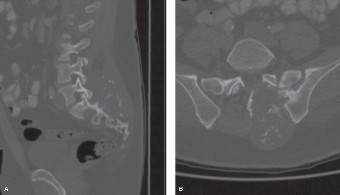

CASE 1 A 63-year-old male sustained a hyperextension injury to his neck while diving into a pool. Upon presentation, he reports decreased sensation in his hands and decreased strength in his arms and wrists, but no lower extremity complaints. On motor examination, he has 5/5 strength in his deltoids and elbow flexors and 4/5 strength in the elbow extensors, wrist extensors, and finger flexors. Lower extremity motor examination is normal. Sensation is decreased to light touch in both hands. Otherwise his sensation is preserved. Images of his cervical spine are shown in Figures 1–1 to 1–3.

The correct answer is (B). The clinical scenario describes a patient with central cord syndrome (CCS). CCS continues to be the most common incomplete spinal cord injury accounting for 15.7% to 25% of all spinal cord injuries. The characteristic presentation is an extension moment injury in a previously spondylotic and stenotic spine. Figures 1–1 to 1–3 demonstrate a spondylotic spine with central narrowing and CSF effacement that is worst at the C3–4 level. Bleeding, edema, and/or Wallerian degeneration lead to damage of the lateral corticospinal tract which is the main descending motor tract in the spinal cord. The more central anatomic position of the homunculus to the upper extremities places them at greater risk than those to the lower extremities. As such, injury to the lateral corticospinal tract is characterized by upper more than lower extremity involvement and motor deficits being more pronounced than sensory deficits.

Figure 1–8 Mid-sagittal image of the pelvis.

Figure 1–9 Axial image of the pelvis.